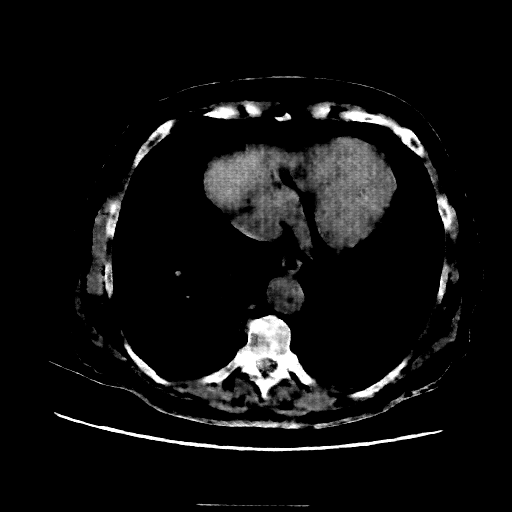

Targeted Slice 70 - Mediastinum Window Analysis (Generated vs Real Venous)

0.666

Mediastinum SSIM

82.6

Mediastinum RMSE

38.4

Mediastinum MAE

Average Mediastinum Window Metrics Across All Slices (107 slices) - Generated vs Real Venous

0.623

Mediastinum SSIM (Avg)

86.1

Mediastinum RMSE (Avg)

43.6

Mediastinum MAE (Avg)

Image Grid

4Γ—3 grid: Rows show different image types (Original NATIVE, Reconstructed NATIVE, Original VENOUS, Generated VENOUS), Columns show windowing techniques (No Window, Lung Window, Mediastinum Window)

Mediastinum window (WL 40, WW 400 β†’ Low βˆ’160, High +240)

Original NATIVE CT scan (input)

Reconstructed NATIVE CT scan (cycle consistency)

Original VENOUS CT scan

Generated VENOUS CT scan (A→B translation)